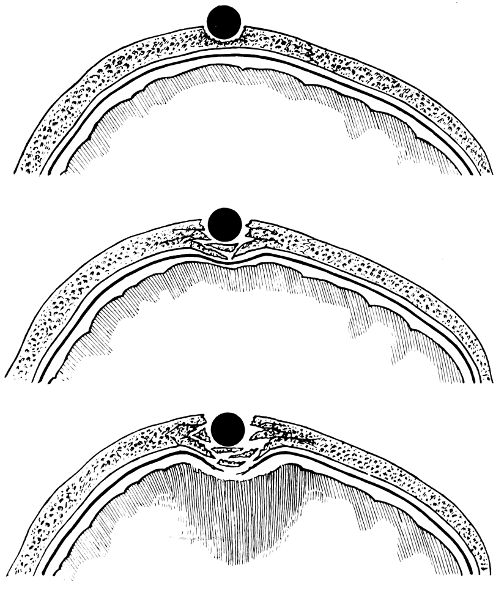

| 51. To illustrate compression of the brain as produced by an extra-dural hæmorrhage from the middle meningeal artery[x] | 141 |

| 52 A and B. The operative treatment of middle meningeal hæmorrhage | 144, 145 |